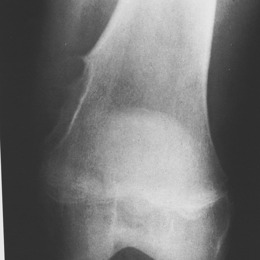

Radiographic imaging is used to help form a diagnosis. These include X-Ray, MRI, CT and Bone Scans.

An example of a X-Ray is shown.